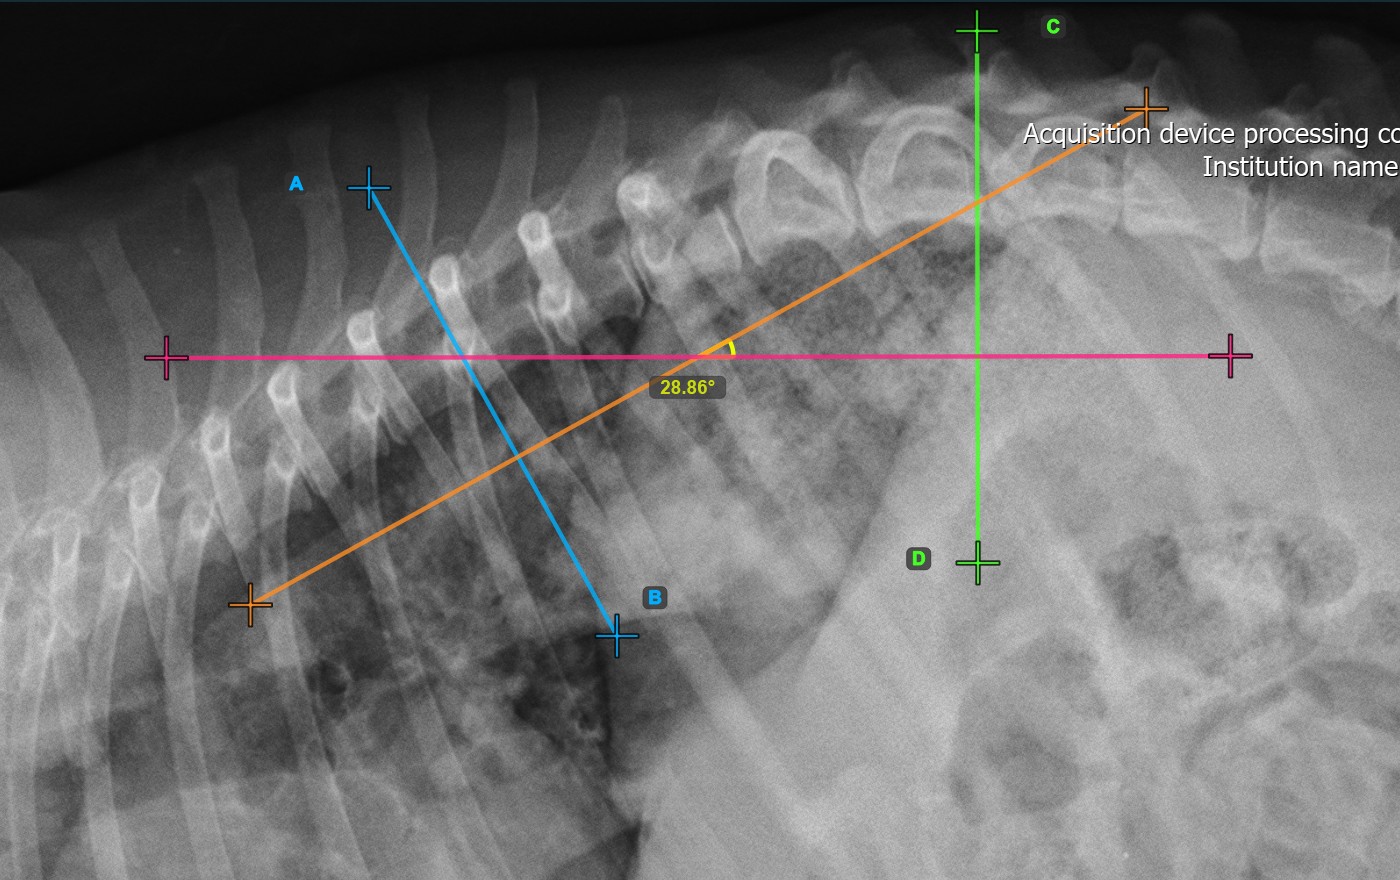

Identify the vertebral endplate at the opposite end of the largest spinal curve deformity. Place the start and end point of the second vertebral line precisely along the identified endplate. Adjust each point on the scene to better align the line with the endplate if needed.

The Cobb Angle measurement will be automatically calculated and completed once the two vertebral lines are placed, indicating the angle of spinal curviture in degrees.

The image below represents a typical placement of the second vertebral line.